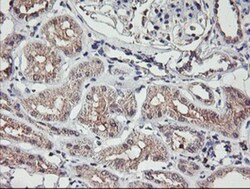

| Antigen | TMEFF2/Tomoregulin-2 |

| Applications | Western Blot, Immunohistochemistry, Immunohistochemistry (Paraffin) |

| Dilution | Western Blot 1:500-2000, Immunohistochemistry 1:150, Immunohistochemistry-Paraffin 1:150 |